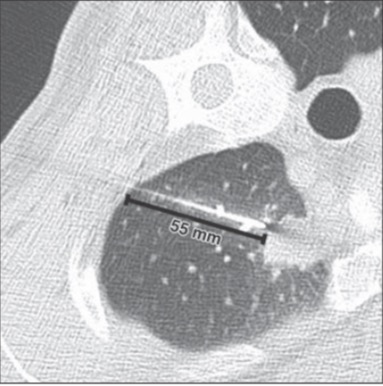

あまり同意できない内容の論文です。Figure1 で左上葉肺癌の穿刺例が示されています。通常なら仰臥位で最短距離である胸骨脇から刺すはずですが(穿刺ルートの長さは気胸の危険因子なので)、側臥位で行っています。後方視的検討なので穿刺経路の選択について明確な基準がないのですが、CTのガントリーの制約で横から刺すのは得策ではないし、結果的に穿刺ルートが長くなっています。結論では喀血時の対側肺保護に有用と書いてありますが今回の研究では検討していない項目で言い過ぎです。肺気腫がひどくて気胸が必発であるような患者で、なおかつ気胸が起きてもどうしても検体が必要な状況ではこのように穿刺側を下にすることはあるかもしれません。